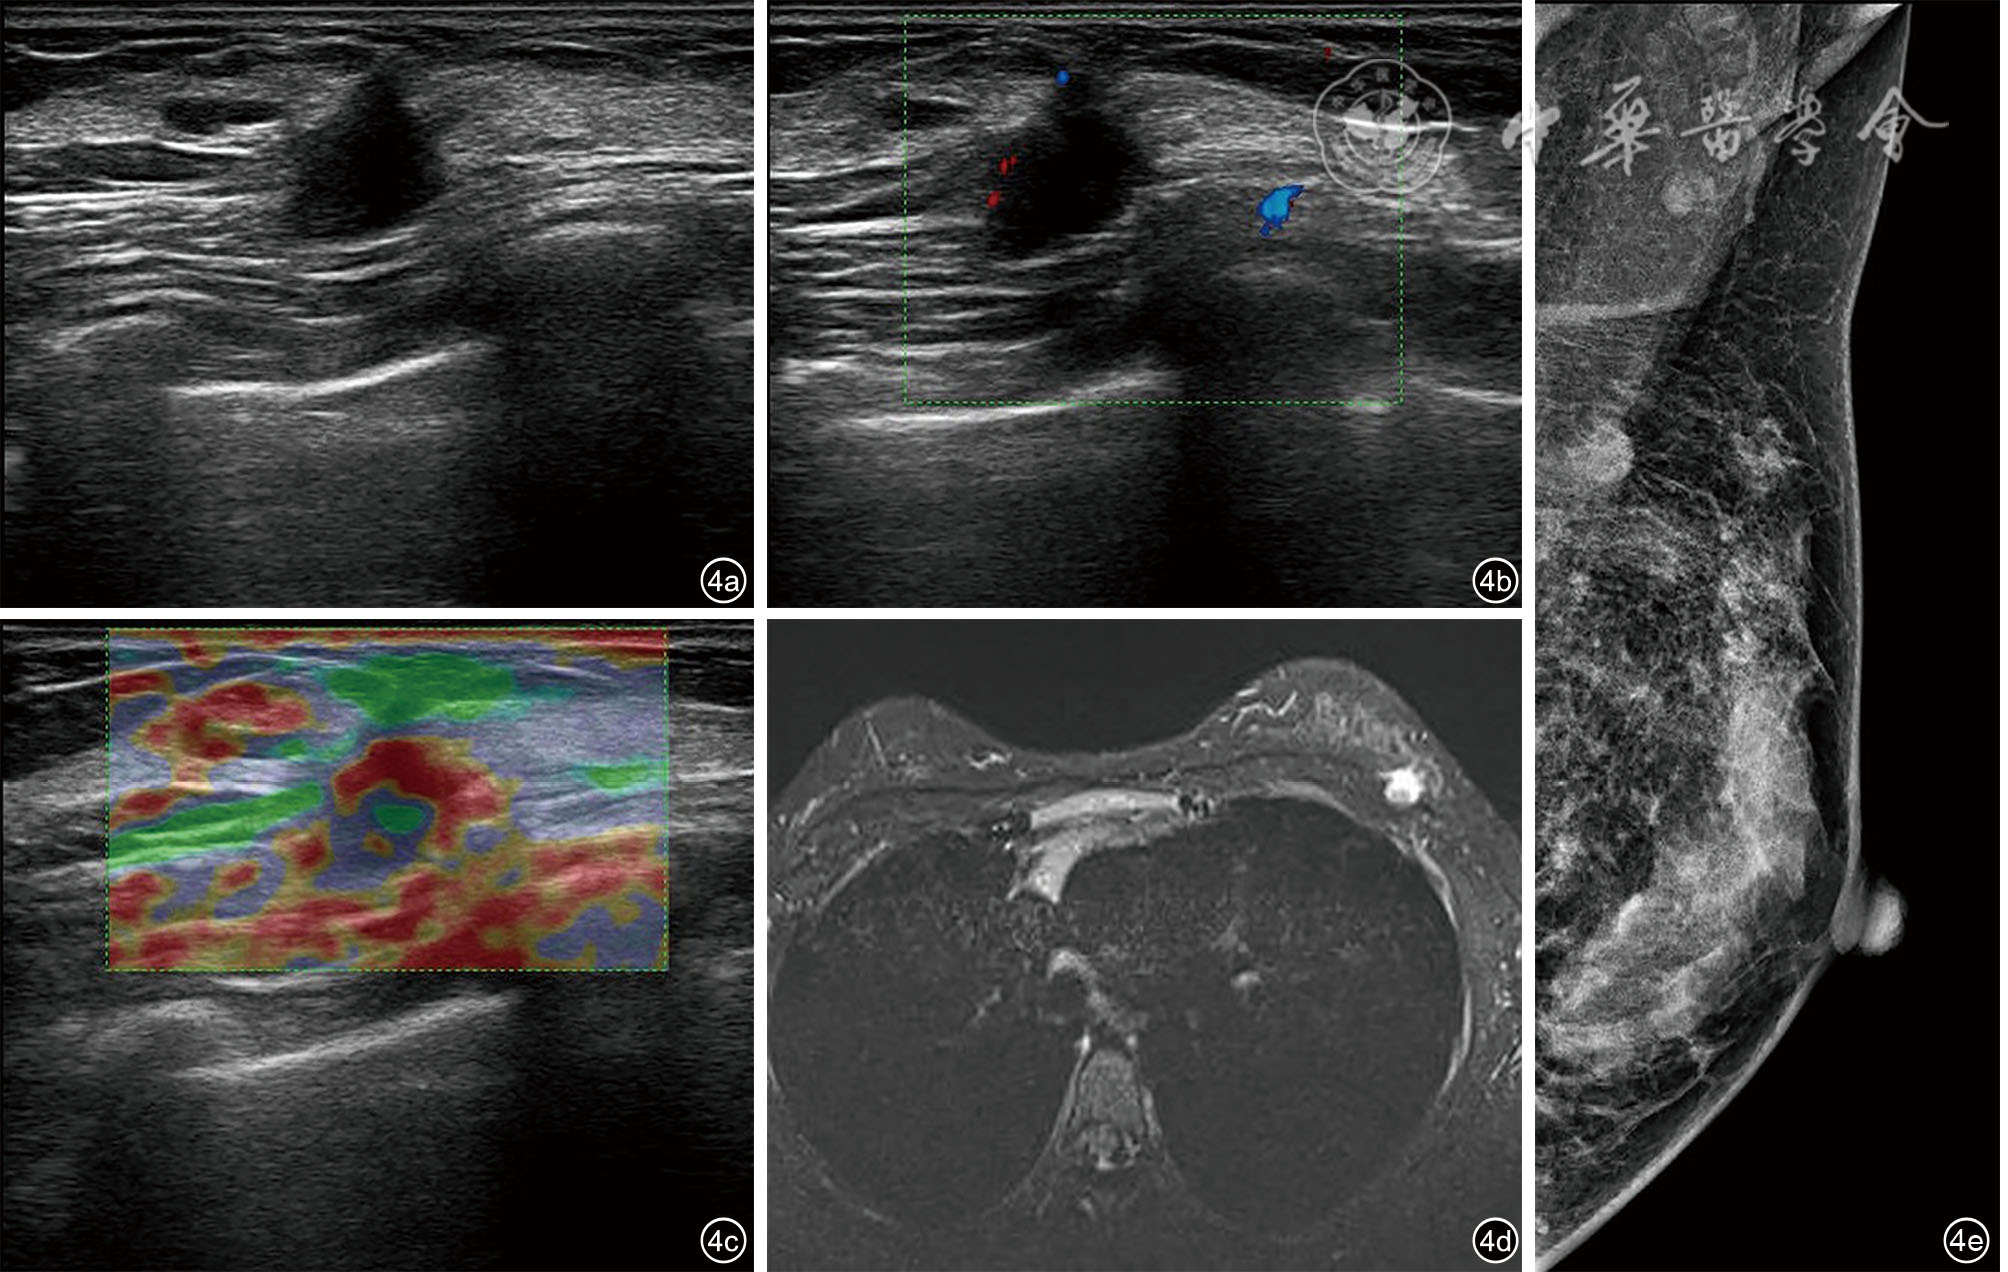

董叶, 彭晓静, 邓晶, 等. 高频超声诊断侵袭性纤维瘤病的应用价值 [J]. 临床超声医学杂志, 2021, 23(1): 69-72.

宗晴晴, 邓晶, 许迪. 乳腺纤维瘤病超声表现与病理结果对照研究及误诊分析 [J]. 肿瘤影像学, 2019, 28(6): 384-389.

Deshwal A, Walton T, Varzgalis M, et al. Imaging modalities used in mammary fibromatosis [J]. Radiol Case Rep, 2023, 18(5): 1949-1953.